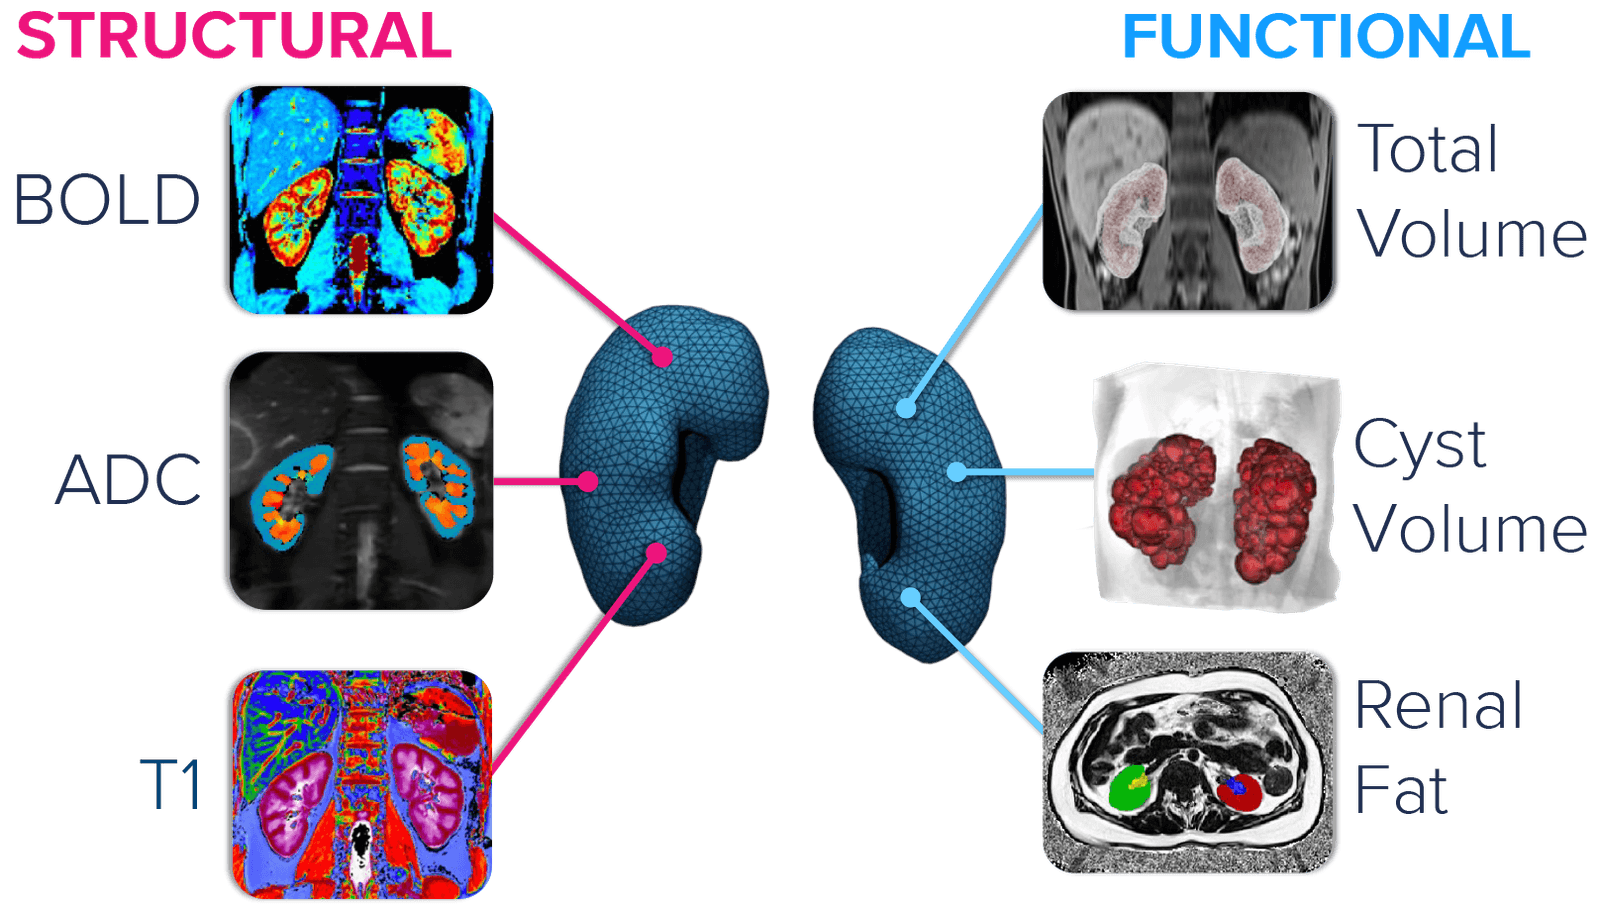

Renal imaging

Our renal imaging suite delivers an extensive assessment of structural and functional metrics that can be used to screen for eligible patients and assess therapeutic efficacy. We bring a rich knowledge base with dedicated experts and a proven track record of innovation in the space of renal imaging, with 30 years of industry experience and 100+ publications in peer-reviewed journals.